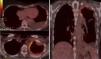

We present the case of a 60-year-old woman who was referred to our pleural pathology outpatient unit due to left pleural effusion. She reported having left-side chest pain with pleuritic characteristics that had been evolving over the course of 8 weeks, with dry cough and general deterioration. Physical exploration included lung auscultation characterized by left basal hypophonesis. The patient had no history of smoking, is a housewife and neither she nor her family members had any type of toxic environmental or occupational exposure, and specifically had no exposure to asbestos. Likewise, her residence was not located near any industries related with asbestos or any other possible asbestos sources. Ten years earlier, she had been treated for infiltrating ductal carcinoma of the breast by means of mastectomy, chemotherapy and radiotherapy. Analyses revealed: ESR 90mm/h, CRP 42.9mg/l, fibrinogen 656mg/dl and CA 15.3 44.1U/ml. Tuberculin prick test was negative. After diagnostic thoracentesis, the liquid met characteristics for lymphocytic exudate, with an ADA of 21IU/l and negative cytology for malignancy. Pleural biopsy with an Abrams needle guided by thoracic ultrasound obtained fragments of pleural and musculoskeletal tissue with no pathologic alterations. Positron emission tomography/computed tomography (PET/CT) showed hyper-uptake in the left apical pleura and in the left basal subpleural area with maximum SUV of 6.8 and 3.8g/ml, respectively (Fig. 1). Given the lack of diagnosis, we performed a CT-guided transthoracic fine-needle aspiration in the area of greatest hyper-uptake on the PET/CT, and cytology showed evidence of the presence of atypical mesothelial proliferation. The final anatomical pathology diagnosis was obtained by pleural biopsy from video-assisted thoracoscopy after having obtained a fragment of tissue compatible with epithelial-type pleural malignant mesothelioma.